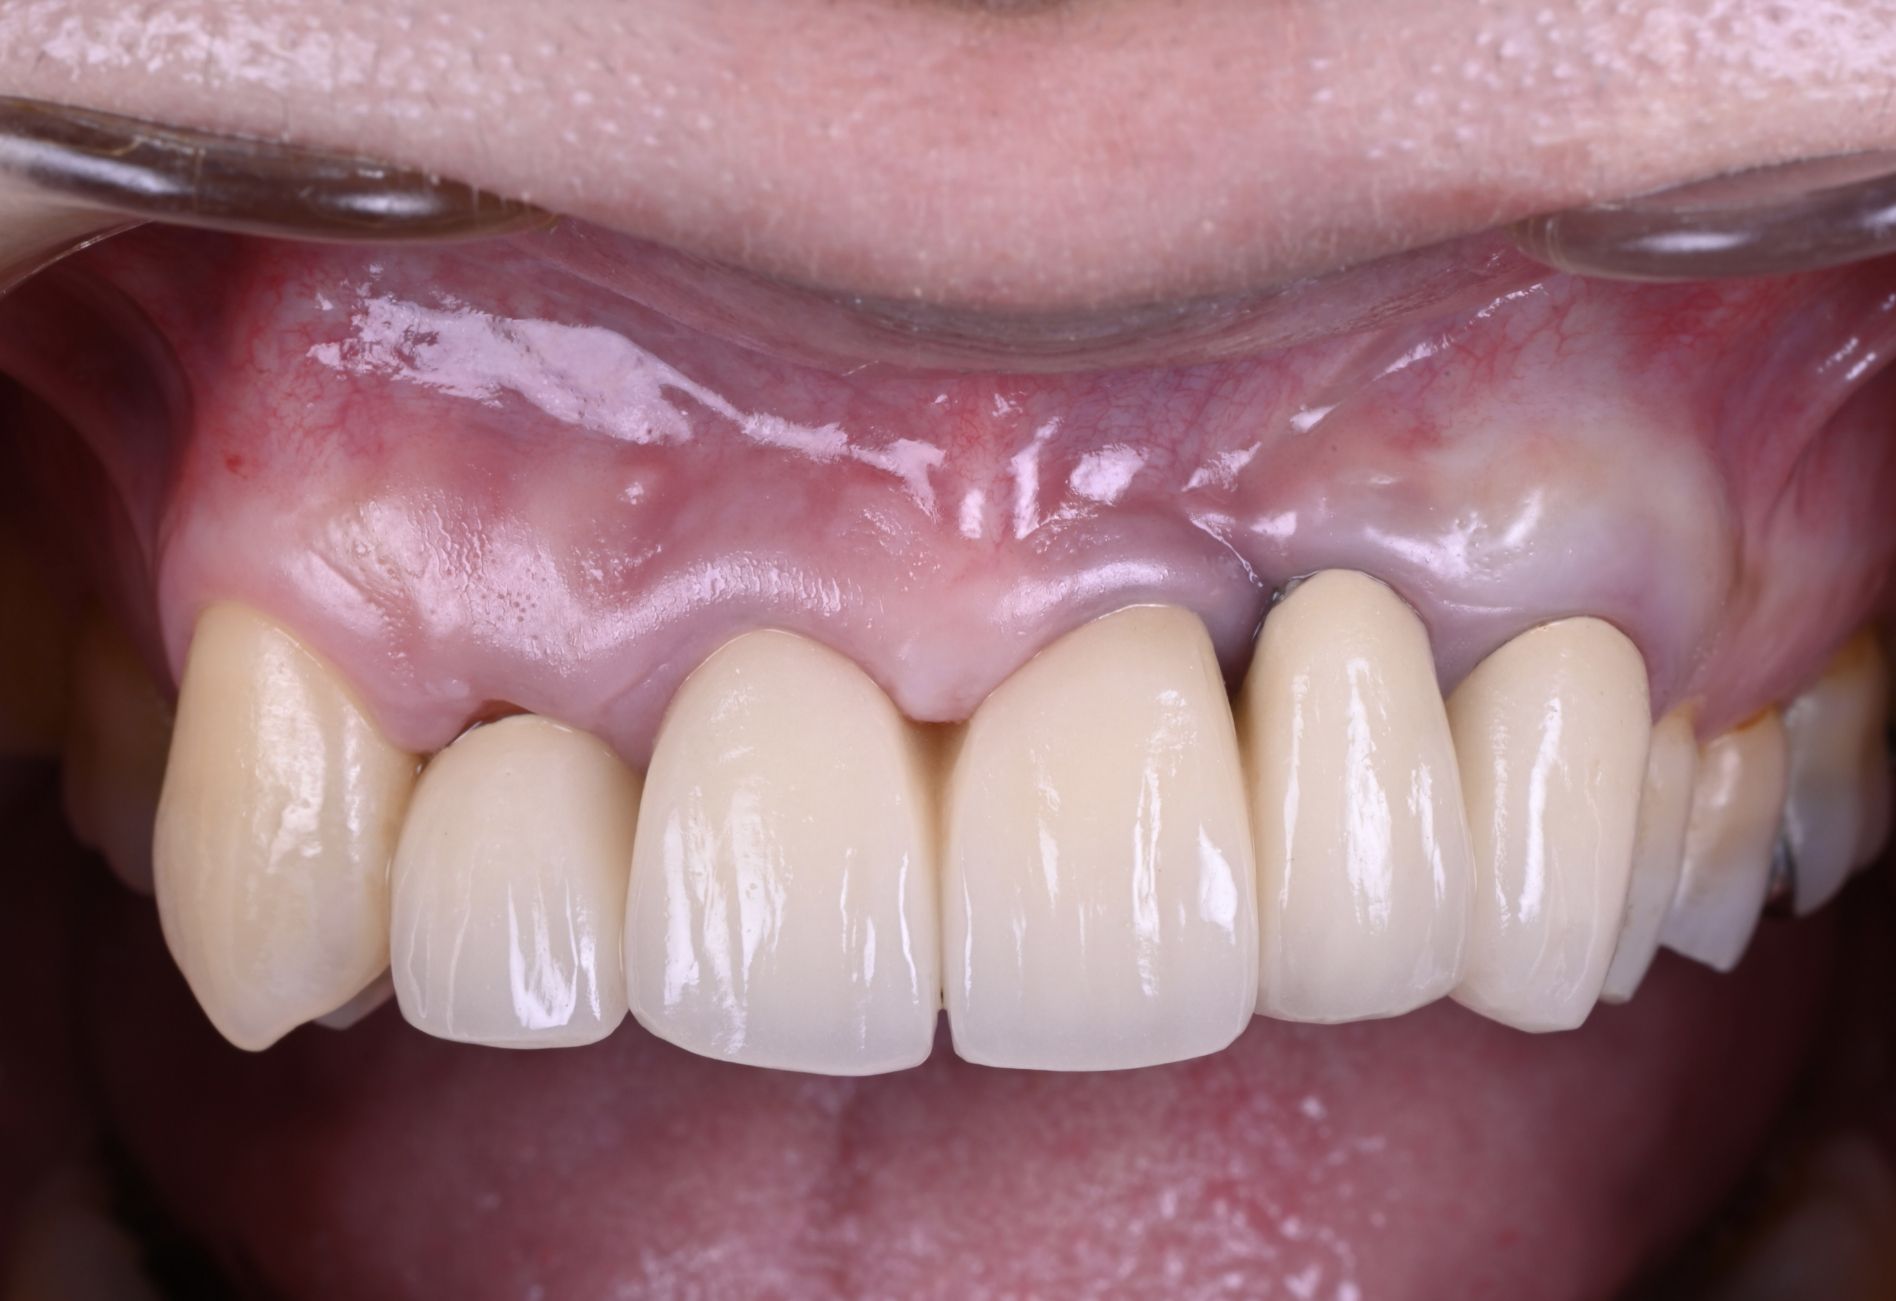

インプラントのやり直しで前歯の審美改善を行った症例

Before

After

年代

30歳代

主訴

前歯のインプラントをやりかえたい。

背景

他院で治療した直後から見た目の仕上がりが気に入らなかった。できるなら自然な見た目に改善して欲しい。

治療

旧インプラント撤去・骨造成・歯肉移植・インプラント治療

治療期間

1年

治療費用

880,000円(税込)